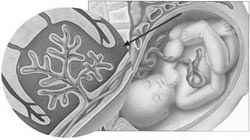

Патология плода у беременных

Курящая женщина подвергает своего будущего ребёнка серьёзному риску. Доказано, что у интенсивно курящих женщин рождаются дети с низкой массой тела. Составляющие сигаретного дыма, попадая в кровь беременной женщины, снижают насыщаемость крови кислородом, что неизменно ведёт к гипоксии – кислородному голоданию плода. Существенно нарушается плацентарное кровообращение: обмен питательных веществ между кровью матери и кровью плода. Выкидыши, преждевременные роды, мёртворождения – удел многих мам, которые не находят в себе сил расстаться с сигаретой. Врождённые пороки развития и уродства плода — частое следствие курения на ранних сроках беременности. Иммунитет деток, рождённых курящими мамами, заметно снижен, синдром ВМС (внезапной младенческой смерти) встречается чаще.